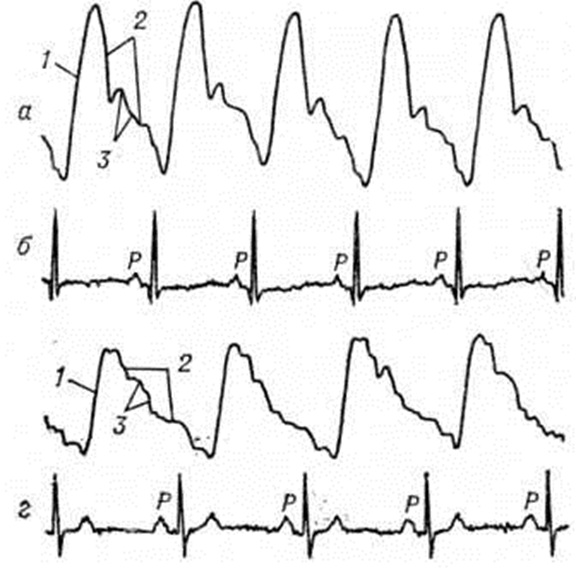

Для определения рентгенофункциональных признаков применяют электрокимографию. На кривой пульсации лёгочного ствола при Гипертензия малого круга кровообращения видна крутая волна подъёма, отражающая наполнение лёгочного ствола, вершина кривой куполообразна. В связи с затруднением опорожнения лёгочного ствола нисходящее колено пологое и образует угол с изолинией.

Дикротический зубец, соответствующий захлопыванию полулунных клапанов, расположен высоко (рисунок 7).

Рентгенокимографическая и электрокимографическая кривые лёгочного ствола при Гипертензия малого круга кровообращения имеют большую амплитуду и напоминают кривую пульсации аорты — так называемый аортолизация лёгочного ствола.